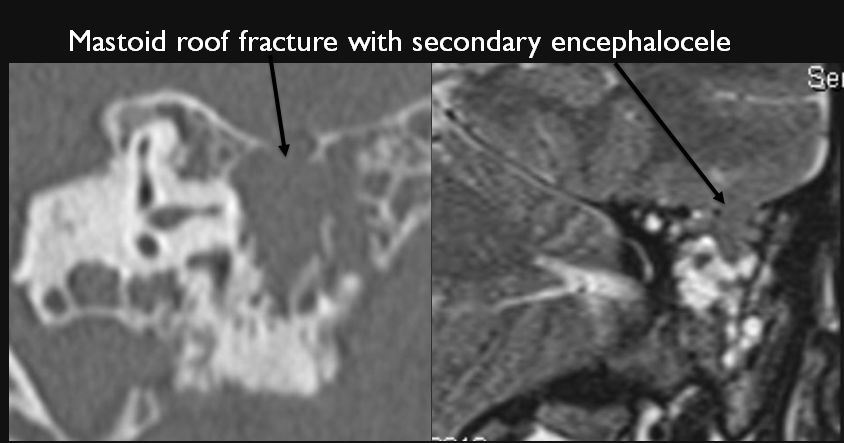

The roof of the mastoid and/or middle ear is fractured.

A possible meningocele and/or encephalocele or CSF leak is present.

There is subperiosteal, epidural or subdural hematoma along the roof of the mastoid or middle ear or the superior and posterior (intracranial) surfaces of the petrous portion of the temporal bone.